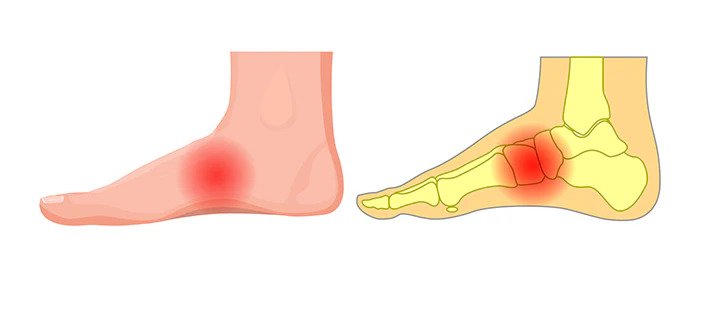

Arch pain can make walking, standing, or daily activities uncomfortable. Whether your pain is caused by flat feet, overuse, or poor foot mechanics, early treatment can help prevent long-term issues.

Arch pain can result from a variety of conditions, including:

- Flat feet (fallen arches)

- High arches (increased pressure on the arch)

- Plantar fasciitis

Common Symptoms

- Pain or soreness in the middle of the foot

- Pain that worsens with standing or walking

- Tightness or strain along the arch